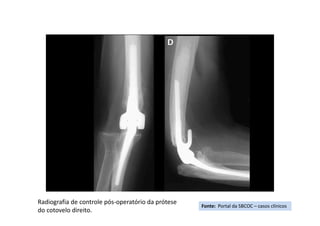

• Tratamento(s): Retirada do fixador externo e artroplastia do cotovelo Direito.

• Seguimento ("Follow up"): Fixador externo retirado após 15 dias para

tratamento definitivo com artroplastia.

Fonte: Portal da SBCOC – casos clínicos

Radiografia inicial da fratura cominutiva do cotovelo

Radiografia de controle pós-operatório da prótese

do cotovelo direito.